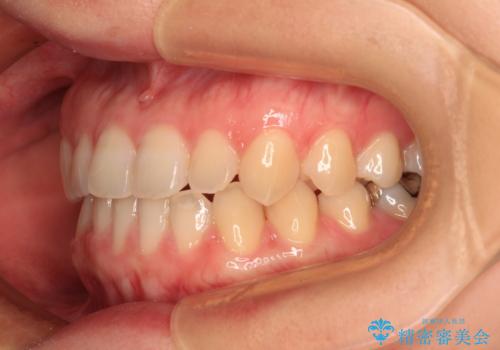

前歯のクロスバイト インビザラインによる矯正治療

- 前歯のクロスバイトとデコボコを気にして来院された患者様です。

骨格的に下顎前突傾向であるため、自己管理が煩わしくないようであれば、インビザラインによる矯正治療がお勧めとなります。

インビザラインを用い、下顎歯列を後方に移動させながら全市の被蓋を改善し、歯並びを整えていくこととしました。

途中マウスピースが使用できず、来院されない期間があり、治療期間は長くかかりましたが、無事に治療を終えることができました。